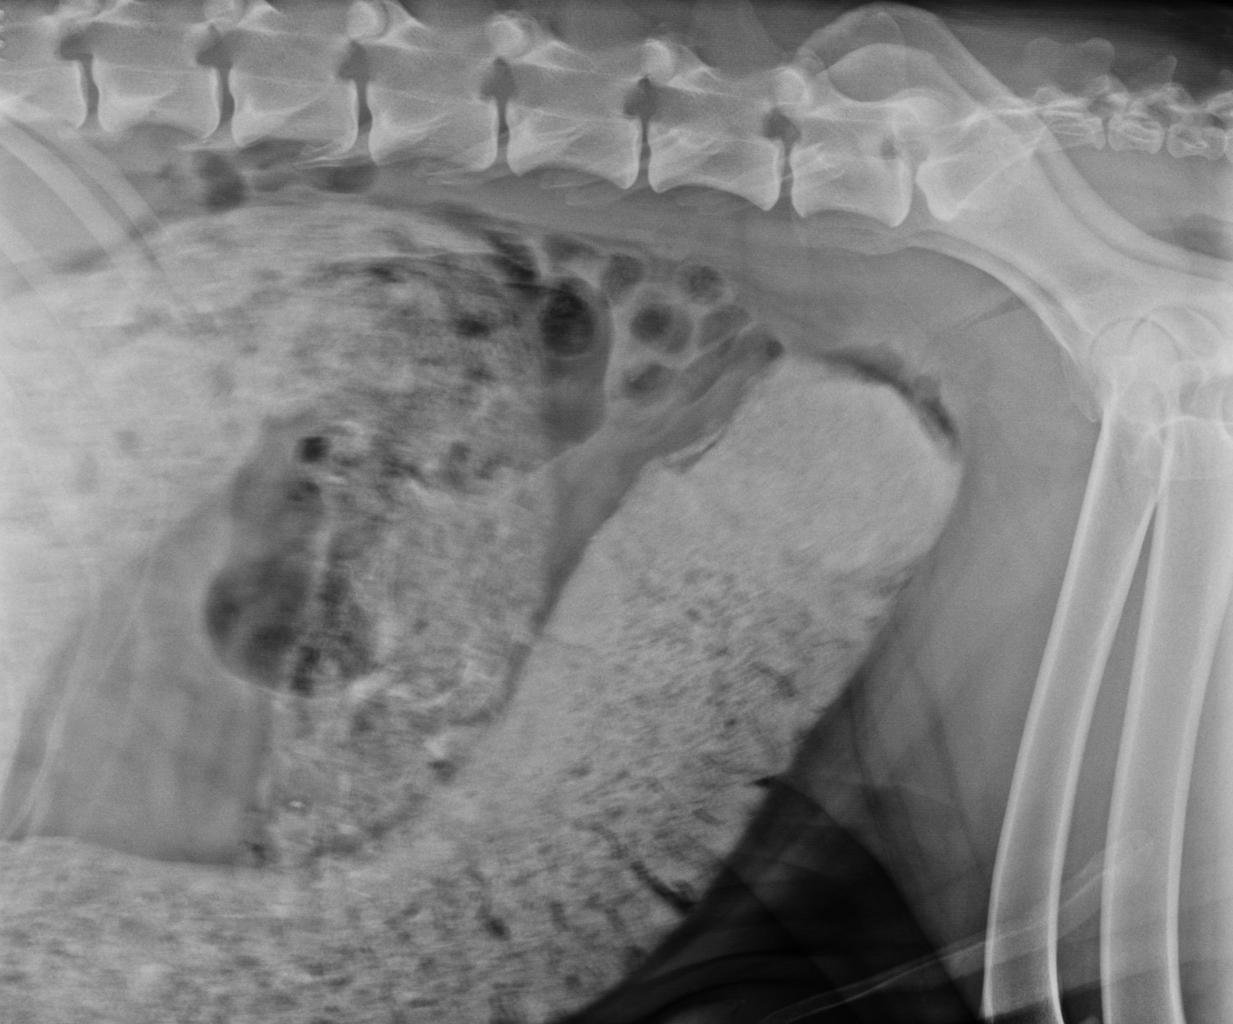

gi foreign body dog

Diagnosis begins with a physical examination and medical history.

At Bushnell Animal Clinic, diagnostic testing may include:

• abdominal radiographs (X-rays)

• ultrasound

• blood tests

Radiographs often help identify the presence and location of the obstruction.